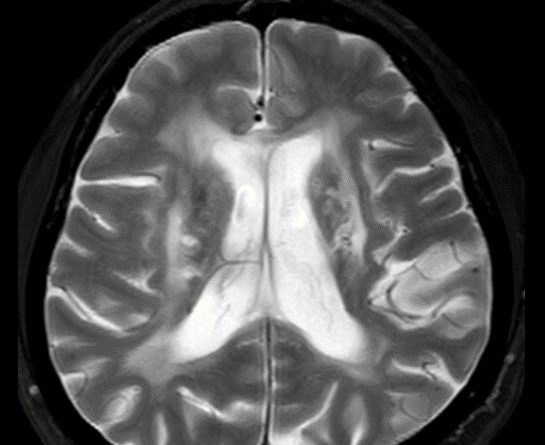

45 yaş, K

4 yıl önce akut sağ hemiparezi, konuşma bozukluğu ve dış merkezde serebellar iskemi tanısı ile ASA kullanımı öyküsü

Konuşma bozukluğu, yersiz gülme ve ağlama atakları, denge kaybı ve uyuşmaları devam ediyor